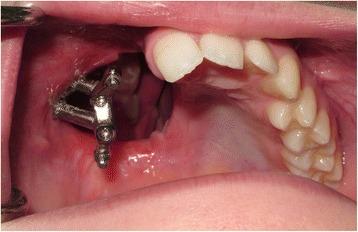

This report details the use of zygomatic oncology osseointegrated implants to support and retain a maxillary obturator in a 13-year-old male patient who underwent a right-sided hemi-maxillectomy (Brown Class 2b) (Brown and Shaw, Lancet Oncol 11:1001-8, 2010) for a myxoid spindle cell carcinoma. At the time of maxillary resection, two zygomatic oncology implants were inserted into the right zygomatic body and subsequently utilised to provide in-defect support and retention for a bar-retained maxillary acrylic obturator prosthesis, which restored the patient's aesthetics and function to a very high level. Close follow-up over 2 years demonstrated ongoing excellent function and disease control with no deleterious effects on facial or dento-alveolar growth clinically. This is the first clinical report of its kind in the published literature detailing the use of a zygomatic implant-retained obturator in a paediatric patient.

本报告详细介绍了在一名13岁男性患者中使用颧骨肿瘤骨整合种植体来支撑和固定上颌阻塞器的情况。该患者因黏液样梭形细胞癌接受了右侧半上颌骨切除术(Brown 2b级)(Brown和Shaw,《柳叶刀·肿瘤学》11:1001 - 8,2010年)。在上颌骨切除时,将两枚颧骨肿瘤种植体植入右侧颧骨体,随后用于为杆式固定的上颌丙烯酸阻塞器假体提供缺损内支撑和固定,该假体将患者的美观和功能恢复到了很高水平。超过2年的密切随访显示,功能持续良好且疾病得到控制,临床上对面部或牙牙槽骨生长无不良影响。这是已发表文献中首例详细介绍在儿科患者中使用颧骨种植体固定阻塞器的临床报告。